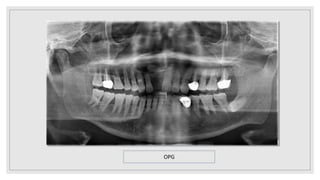

OPG

• #41 OPG revealed a well defined radiolucency of size measuring 2*2cm at apex of 12,11,21 extending mediolaterally from mesial aspect of 13 to distal aspexct of 22 and superioonferiorly from floor of nasal cavity to apex of roots of 11,12,21. internal structures is complete;ly radiolucent with a radiopaque mass resembling morphology of tooth suggestive of supernumerary tooth. Effect on adjacent structures shows no abnormality.